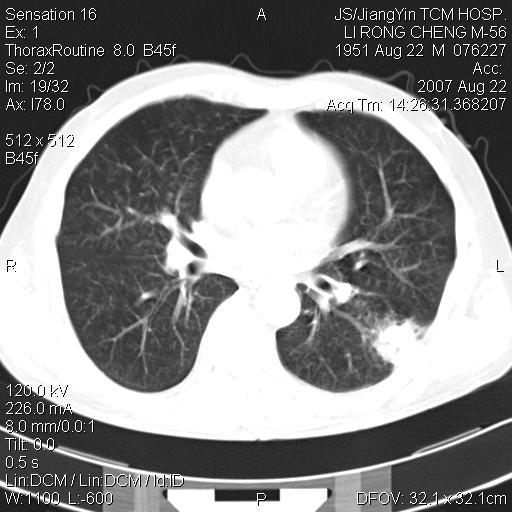

标题: CT9479:M,56Y,DM病史,咳嗽发热5天.肺脓疡.肺癌? [打印本页]

标题: CT9479:M,56Y,DM病史,咳嗽发热5天.肺脓疡.肺癌?

边灶边缘较光整,冠状位病灶呈大片状,,内有空洞,有胸膜反应,但无明显胸膜外侵犯征像,结合病史支持考虑肺肿脓,不排除结核,治疗后复查

好多钙化灶哦,病灶位于下叶背段,或许考虑结核更合适,做下相应检查先

左肺下叶见类软组织密度影,其内密度不均,有小空洞,广基与胸膜相连,其周见斑片状致密影.

考虑肺肿脓,不排除结核.

左肺下叶支气管呈小囊状扩张。下叶背段有类圆形高密度影,边缘模糊,外与胸膜相连。左侧胸膜增厚粘连。心包膜增厚。结合病史考虑1支扩并感染2胸膜及心包炎。

左下肺团片状类软组织密度影,形态不规则,边缘欠规整,其内可见液化区及气体影,病灶内侧见引流支气管影,相邻胸膜反应性增厚。病灶周围肺野内见增粗支气管,壁厚,边缘模糊。考虑:支气管扩张并感染;肺脓肿。